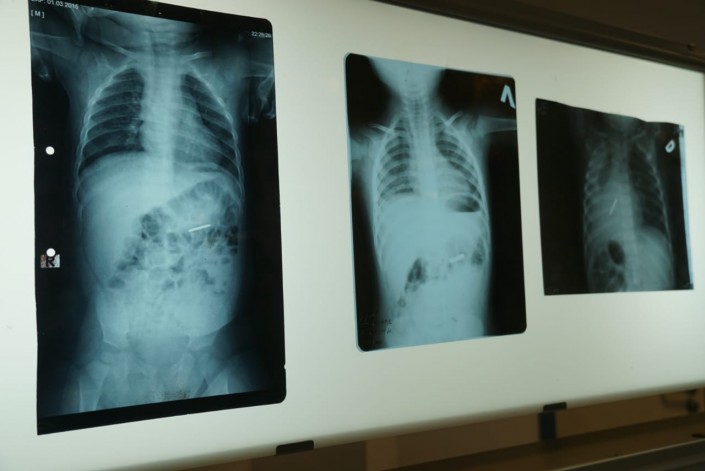

Рентген-снимки ребенка с инородным предметом в организме